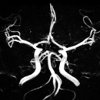

“Brave Dreams letteralmente significa Sogni Coraggiosi. In realtà indica la sigla BRA.VE DR.E.A.M.S, abbreviazione di BRAin VEnous DRainage Exploited Against Multiple Sclerosis, che, tradotto dall’inglese, significa sfruttare il drenaggio venoso contro la Sclerosi Multipla”, spiegano i sostenitori del metodo Zamboni: “Nel 90% dei casi – si legge sempre sul sito web della campagna – i malati di Sclerosi Multipla hanno le vene del collo e del torace occluse a causa di una malattia vascolare chiamata CCSVI. Nei malati di CCSVI, il sangue non ossigenato proveniente dal cervello e dal sistema nervoso centrale fatica ad arrivare al cuore a causa di ostacoli venosi e restringimenti vari. Un semplice intervento di angioplastica dilatativa (PTA), ripristinando il normale circolo venoso, può fermare la Sclerosi Multipla e attenuarne i sintomi. Affinché ciò sia definitivamente provato occorrono studi clinici”.